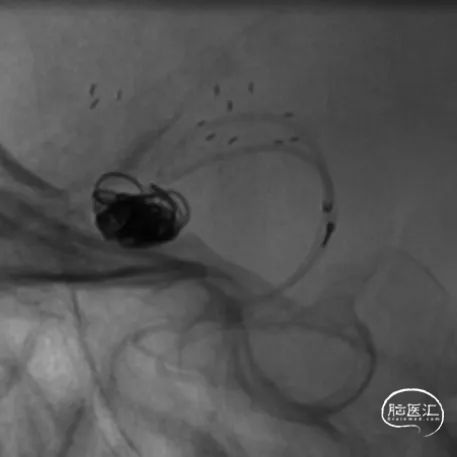

经下干的SL-10微导管释放第二枚Atlas支架,形成“Y”型支架形态,充分保护上下两干,Atlas支架打开顺畅,影像下可清晰看到两端标记点完全打开。第二枚支架释放完毕后,顺势将该SL-10微导管经支架网眼顺利超选入瘤腔,拟双微管填塞。经一根SL-10微导管释放第一枚Target XL 4mm*12cm弹簧圈进行成篮。

相继填入Target系列弹簧圈,型号分别为2mm*8cm、2mm*6cm(两枚)、1.5mm*4cm(两枚)。